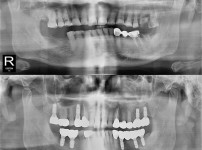

种植牙

局部种植牙